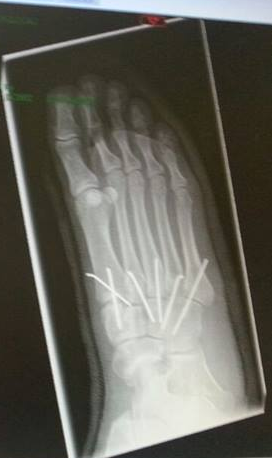

Meteen een operatie gehad. De dokters hadden nog zo gezegd dat ik geen pinnen in mijn voeten zou krijgen ( Heb ik in mijn halve Duits gehoord ). De operatie was goed gegaan, maar de nabehandeling in het ziekenhuis was heel slecht. Niemand die naar mij toe kwam wat ze hadden gedaan met mijn voet. Het verband eraf halen en vervolgens een half uur openlaten waardoor, ik de vliegen die neerstreken op mijn been, moest wegslaan.

Na een week ging ik in Nederland naar de afdeling chirurgie. Foto's bekijken, voelen, hechtingen eruit. Nadat de dokter de foto's had bekeken zei hij er zitten 6 pinnen in je voet. Pinnen in mij voet ?!, dacht ik. Een kleine teleurstelling.. want, waar ik zo bang voor was, was nog een operatie. Ook hier kreeg ik weer te horen dat het 1 van de ernstigste letsels was, wat je maar kon hebben.